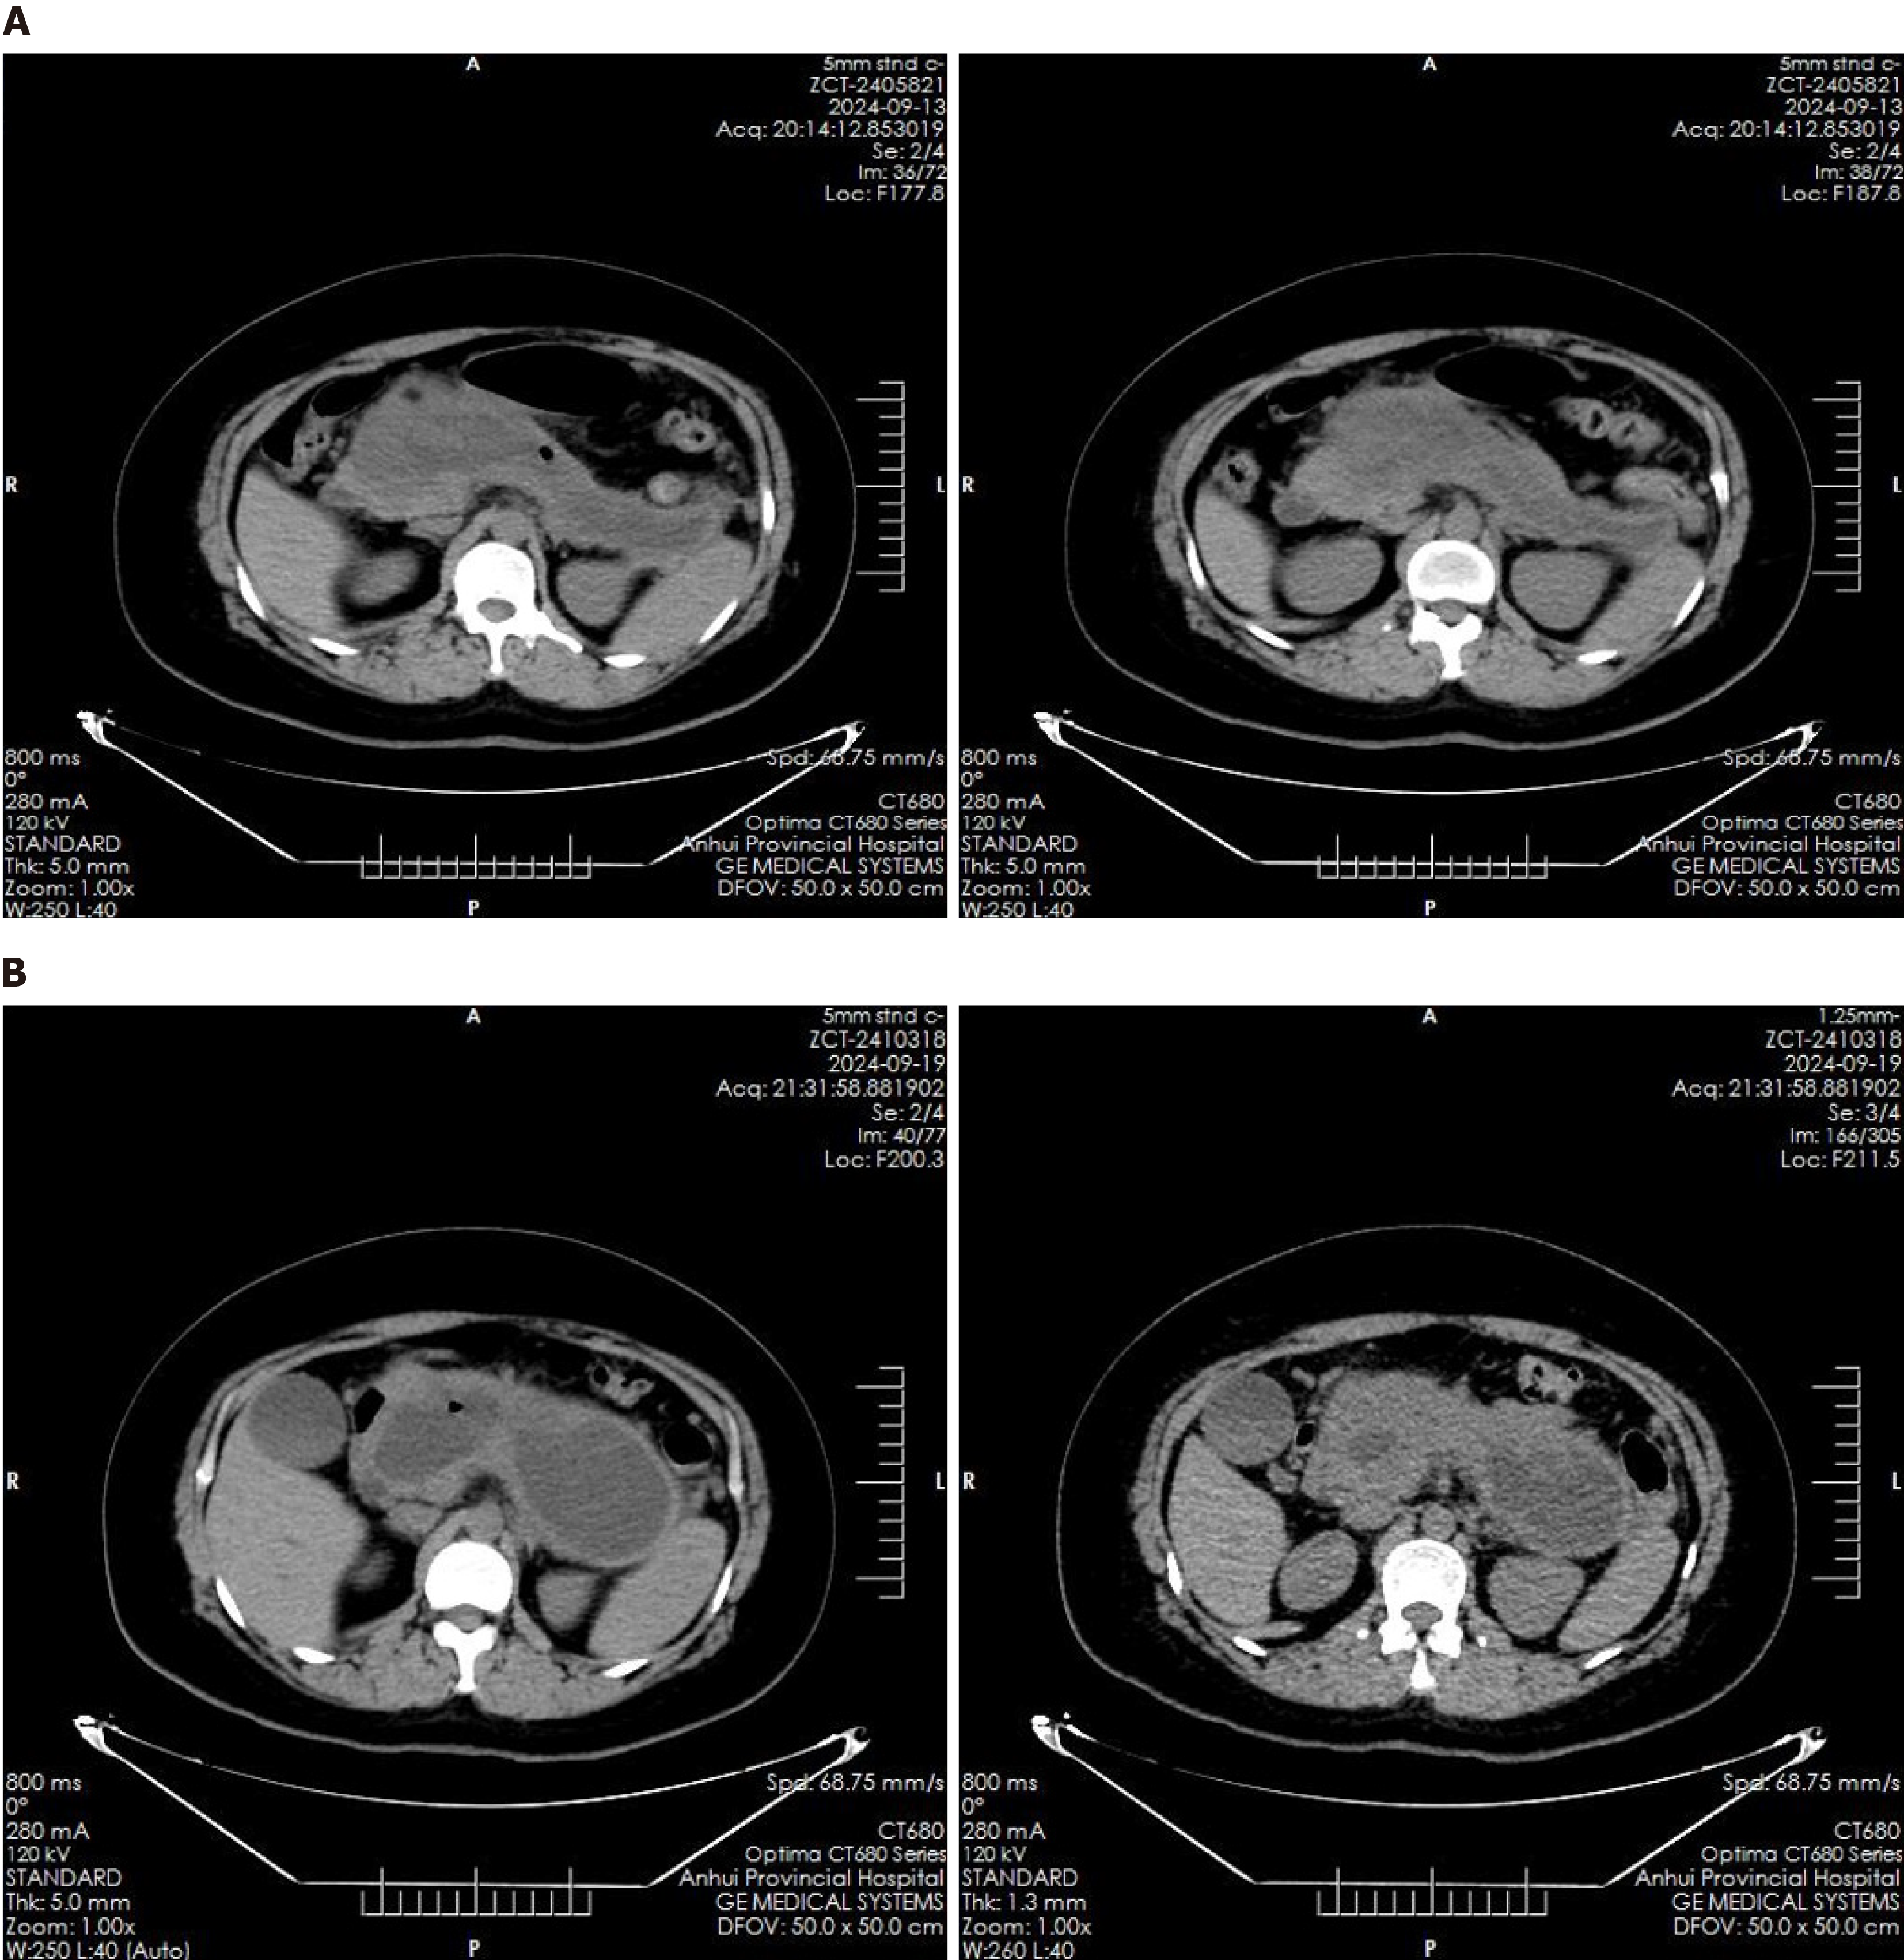

Abdominal ultrasound revealed multiple echogenic clusters with acoustic shadows in the gallbladder, the largest measuring approximately 12 mm × 8 mm. The pancreas exhibited clear, non-echogenic changes, measuring approximately 231 mm × 135 mm × 109 mm. Auxiliary examinations included an enhanced CT scan of the upper abdomen, which revealed an irregular, elliptical cystic low-density shadow approximately 232 mm × 114 mm in size, located in the pancreatic region, with no significant dilation of the intrahepatic or extrahepatic bile ducts (Figure 1). Additionally, multiple gallstones were identified in the gallbladder. Magnetic resonance imaging findings confirmed the presence of a pancreatic cyst and gallstones.

Post-procedure imaging via CT scan, conducted eight hours after the endoscopic intervention, demonstrated complete resolution of the pancreatic cyst (Figure 5A). A follow-up CT scan on the sixth postoperative day indicated the re